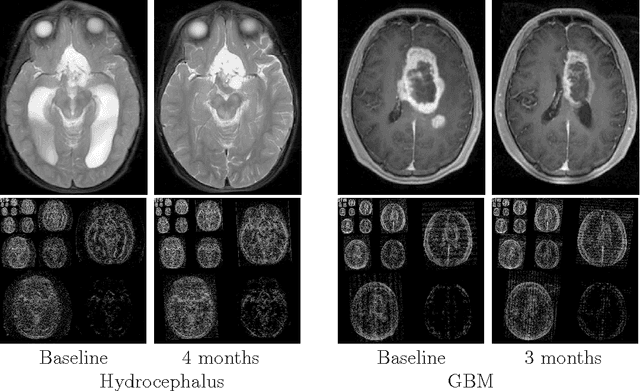

Abstract:Purpose: Repeated brain MRI scans are performed in many clinical scenarios, such as follow up of patients with tumors and therapy response assessment. In this paper, the authors show an approach to utilize former scans of the patient for the acceleration of repeated MRI scans. Methods: The proposed approach utilizes the possible similarity of the repeated scans in longitudinal MRI studies. Since similarity is not guaranteed, sampling and reconstruction are adjusted during acquisition to match the actual similarity between the scans. The baseline MR scan is utilized both in the sampling stage, via adaptive sampling, and in the reconstruction stage, with weighted reconstruction. In adaptive sampling, k-space sampling locations are optimized during acquisition. Weighted reconstruction uses the locations of the nonzero coefficients in the sparse domains as a prior in the recovery process. The approach was tested on 2D and 3D MRI scans of patients with brain tumors. Results: The longitudinal adaptive CS MRI (LACS-MRI) scheme provides reconstruction quality which outperforms other CS-based approaches for rapid MRI. Examples are shown on patients with brain tumors and demonstrate improved spatial resolution. Compared with data sampled at Nyquist rate, LACS-MRI exhibits Signal-to-Error Ratio (SER) of 24.8dB with undersampling factor of 16.6 in 3D MRI. Conclusions: The authors have presented a novel method for image reconstruction utilizing similarity of scans in longitudinal MRI studies, where possible. The proposed approach can play a major part and significantly reduce scanning time in many applications that consist of disease follow-up and monitoring of longitudinal changes in brain MRI.